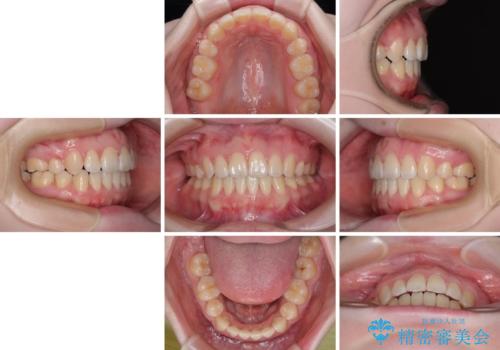

口元の突出感が改善されてことで、下唇に引っかかっていた上顎前歯も気にならなくなりました。

強い舌の突出癖により、上下前歯が前方に飛び出しており、特に上顎前歯は下顎よりも更に前方に位置している状態でした。

上顎前歯をしっかりと後方に移動させるため、口蓋側にアンカースクリューと補助装置を併用し、上下左右の第一小臼歯4本を抜歯し、ワイヤー装置にて矯正治療を行うこととしました。